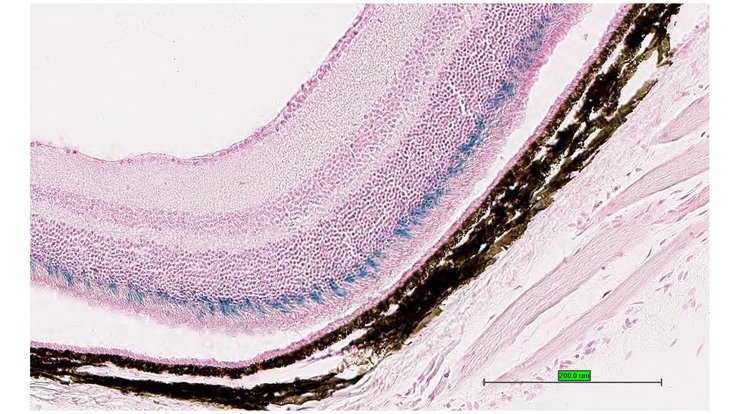

Specimen UC Davis_1877111: postnatal adult; Cabp4tm1.1(KOMP)Vlcg/Cabp4+ (more )

Structure Level Pattern Image Note

TS28: eye Present UC Davis_1877111

Specimen UC Davis_1877112: postnatal adult; Cabp4tm1.1(KOMP)Vlcg/Cabp4+ (more )

TS28: eye Present UC Davis_1877112

Specimen UC Davis_1877114: postnatal adult; Cabp4tm1.1(KOMP)Vlcg/Cabp4+ (more )

TS28: eye Present UC Davis_1877114

Specimen UC Davis_1877115: postnatal adult; Cabp4tm1.1(KOMP)Vlcg/Cabp4+ (more )

TS28: eye Present UC Davis_1877115